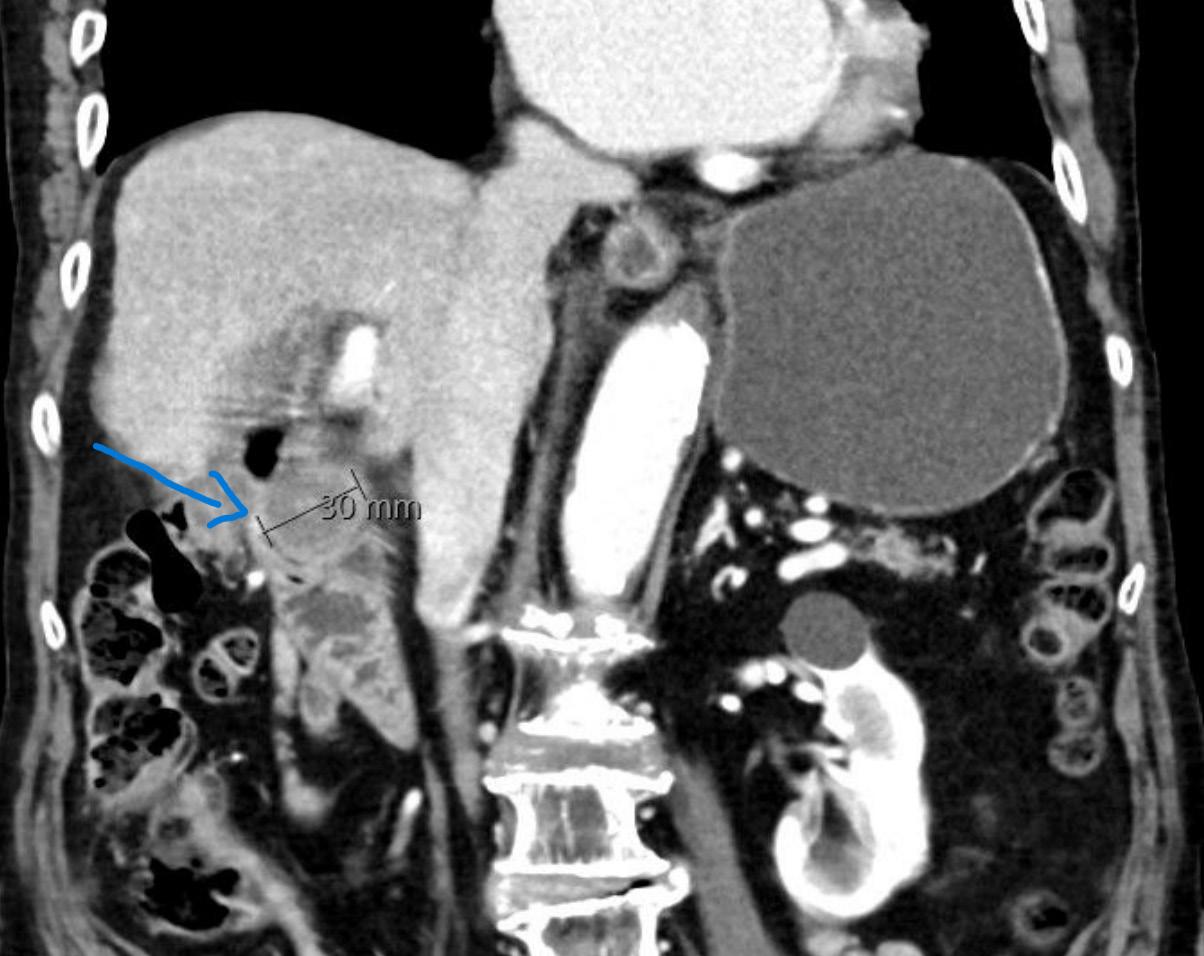

CT thorax/abdomen/bekken 16 måneder etter sykdomsdebut viste ingen tegn til persisterende sykdom. Imidlertid hadde pasienten fått smerter i skulder og 17 måneder etter sykdomsdebut ble det påvist en 4,5 cm stor metas-

2: MR høyre skulder 14 måneder etter sykdomsdebut viste metastase i humerus. Den ble initial strålebehandlet med noe bedring av smertene. Etter hvert tilkom det påny vekst og smerter, og pasienten ble operert med protese etter åtte måneder. Samtykke til publisering av røntgenbilde er innhentet fra pasientens ektemann da pasienten er død.

tase i humerus (Bilde 2). Biopsi bekreftet metastase fra anaplastisk karsinom. NTRAK 1-3 fusjon og RET fusjon/ mutasjon var negative. Pasienten fikk strålebehandling 4 Gy x 7 mot metastase i humerus. Medikasjon ble endret til encorafenib 150 mg og bimetinib 45 mg x 2. Åtte måneder senere ble hun operert med fjerning av tumor i humerus og implantasjon av skulderprotese på grunn av økende vekst og smerter.